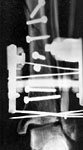

From: chris wilson

Thank you all for your interest. A lot of list members are telling me to fix the fibula and raise and graft the tibial plafond. I enclose 2 other small images to convince you that the fibula is intact and the tibial metaphsis has been well reduced, and in these circumstances is there any thing we can do about the talar tilt and to improve the prospects of avoiding post-traumatic OA?